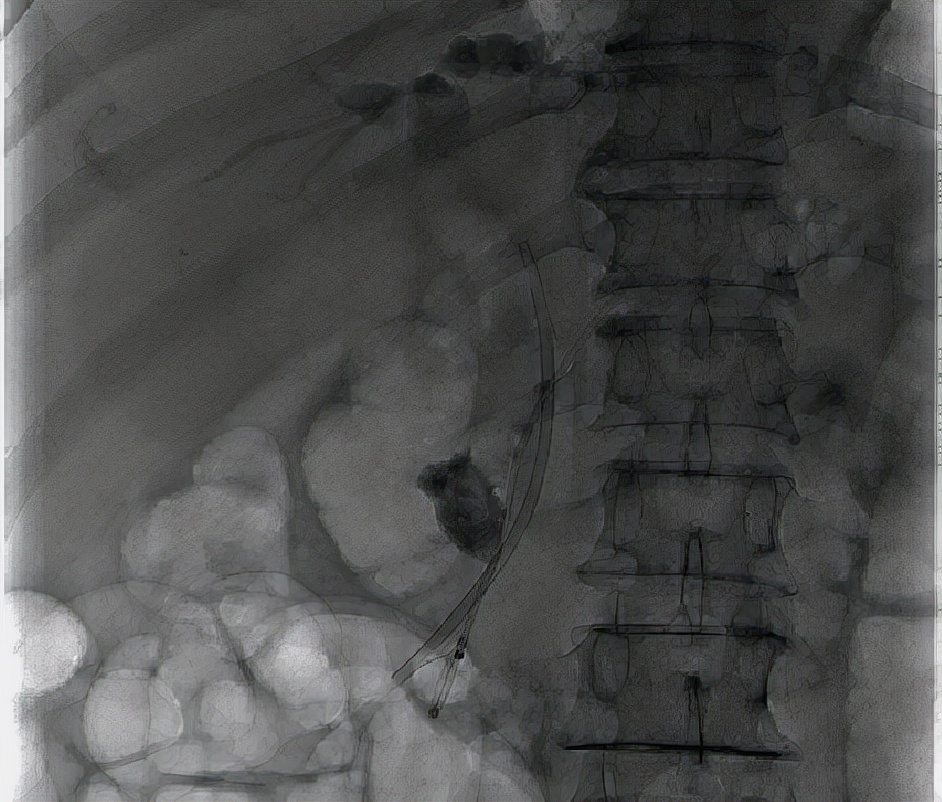

手术过程中,章诺贝教授在经内镜下对胰管插管造影后发现胰管起始部见数个大小不等的充盈缺损影,最大者为23mm*15mm。胰管内的巨大结石,这无疑为手术加大了难度。紧急情况下,手术团队决定施行乳头小切开,经反复对胰管进行扩张后,顺利越过梗阻部位至远端胰管并置入胰管支架,胰液引流通畅并见较多蛋白栓子随胰液流出,同时在胆管置入胆管支架,大量墨绿色胆汁通过胆道支架流出,手术十分成功,术后患者恢复良好。